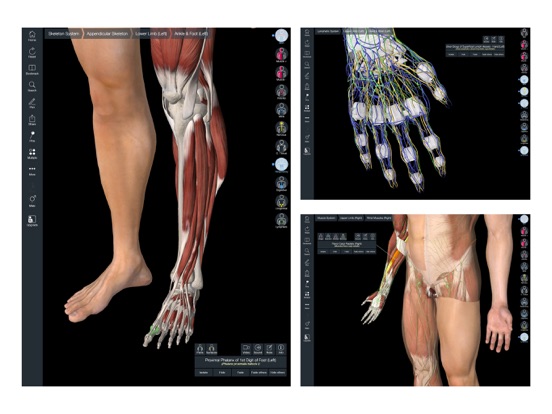

Downloading Essential Anatomy 5 IPA for iOS is a convenient and useful way to explore the world of human anatomy right from the comfort of your iPhone or iPad. This app provides a comprehensive and detailed view of the human body, allowing users to interact with various systems and structures. With stunning 3D graphics, it offers a visually captivating experience that aids in understanding and learning about the complexities of the human body. Whether you are a medical student, healthcare professional, or someone with a general interest in anatomy, Essential Anatomy 5 IPA is a must-have app that provides a wealth of knowledge at your fingertips. The app’s intuitive interface and easy navigation make it accessible to users of all levels of expertise. With just a few taps, you can delve into different layers of the body, explore various organs, muscles, and bones, and gain a deeper understanding of human anatomy. Download Essential Anatomy 5 IPA today and elevate your knowledge and appreciation of the human body.

The Essential Anatomy 5 IPA for iPhone is an incredible tool for medical students, professionals, and anyone interested in learning more about the human body. This app provides a comprehensive and detailed 3D model of the human anatomy, allowing users to explore and study different parts of the body with ease. With its user-friendly interface and interactive features, users can zoom in, rotate, and examine every angle of the human body, from bones and muscles to organs and systems. The app also provides in-depth information about each structure, making it a valuable resource for studying and understanding the intricacies of human anatomy. Whether you’re a medical student preparing for exams or simply curious about the wonders of the human body, the Essential Anatomy 5 IPA for iPhone is an essential tool to have at your fingertips.

Essential Anatomy 5 IPA MOD IOS is a revolutionary app that has changed the way we learn about the human body. With its advanced features and stunning visuals, this app provides an immersive and interactive experience for users. Whether you are a medical student, healthcare professional, or simply interested in learning about anatomy, Essential Anatomy 5 is a must-have tool. It offers a comprehensive library of detailed 3D models, allowing users to explore every aspect of the human body. From the skeletal system to the muscular system, nervous system to cardiovascular system, this app covers it all. Additionally, it provides in-depth information on each structure, including names, functions, and clinical relevance. With its user-friendly interface and intuitive controls, navigating through the app is a breeze. Overall, Essential Anatomy 5 IPA MOD IOS is an essential resource that brings anatomy to life, making it an invaluable tool for anyone interested in the human body.

This app provides a comprehensive and detailed 3D representation of the human body. With over 8,200 anatomical structures, including muscles, bones, organs, and more, it offers a level of accuracy and depth that is unparalleled. Whether you are studying for an exam or explaining a medical condition to a patient, Essential Anatomy 5 IPA has the information you need.

Essential Anatomy 5 IPA allows users to interact with the 3D models, zooming in and rotating them to explore every angle. The user-friendly interface makes navigating through the app a breeze, and the intuitive controls ensure that anyone, regardless of their level of expertise, can easily explore and understand the complex anatomical structures.